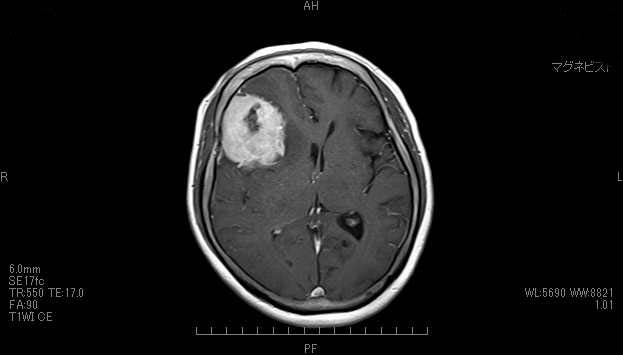

04 脳腫瘍 開頭脳腫瘍摘出術

脳腫瘍(のうしゅよう)とは?

脳腫瘍にも、良性や悪性があります。良性のものは、手術できれいに取ると普通の生活に戻ることが可能です。

開頭脳腫瘍摘出術

頭蓋骨を開けて腫瘍を取り除きます。その他に、放射線治療などを行うこともあります。

脳腫瘍術前

脳腫瘍術後